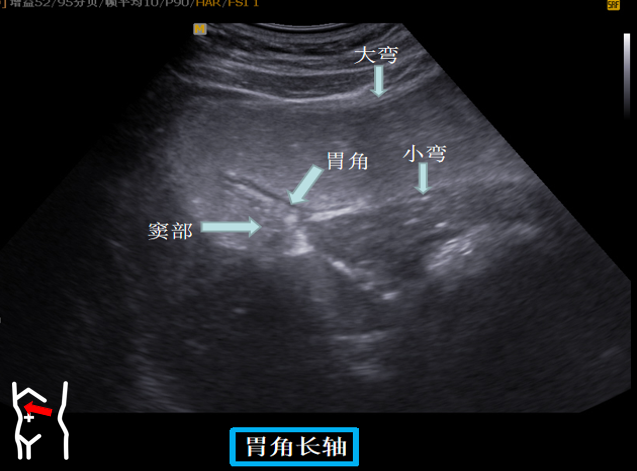

第三组胃体切面

患者取右侧卧位探头从左肋缘下朝左上方翘找出脾下缘以其为起点原位逆时针扇扫依次可见胃底贲门胃体长轴短轴胃体胰腺胃角长轴胃角短轴胃角切迹是胃体与胃窦分界这组切面同时可以观察到胃窦有时还可以观察到球部。